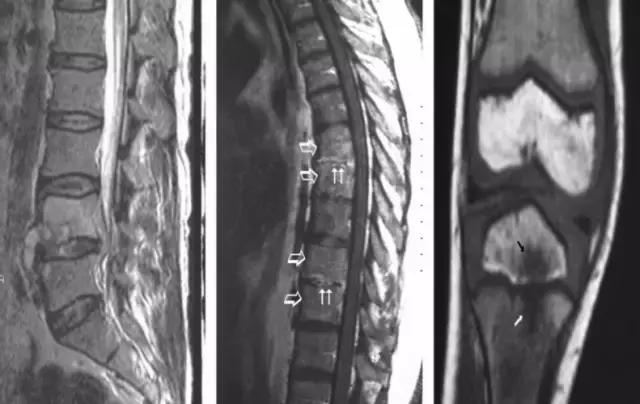

慢性「布鲁氏菌病」主诉症状有:间歇性背痛、关节痛、发汗、精神、神经症状和葡萄膜炎。随着病情进展,骨骼关节破坏慢慢显现。虽然脊柱(尤其是腰椎)破坏较为常见,其他大关节、小关节骨骼破坏见诸报道。